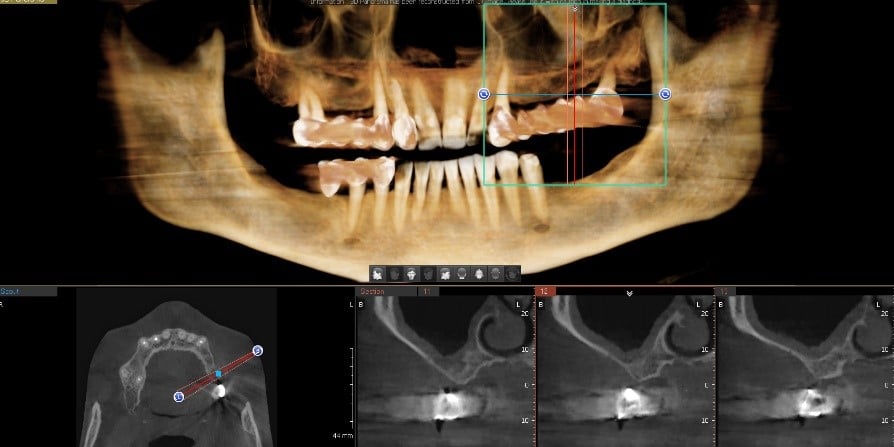

În urma evaluării CBCT-ului s-a constatat necesitatea realizării augmentarii osoase ăn zona posterioară maxilară, lifting sinusal maxilar bilateral odată cu inserarea implanturilor.

Medicul specialist a efactuat scanarea digitală a arcadelor pe care a trimis-o tehnicianului dentar DigiRay, împreună cu CBCT-ul pacientului.